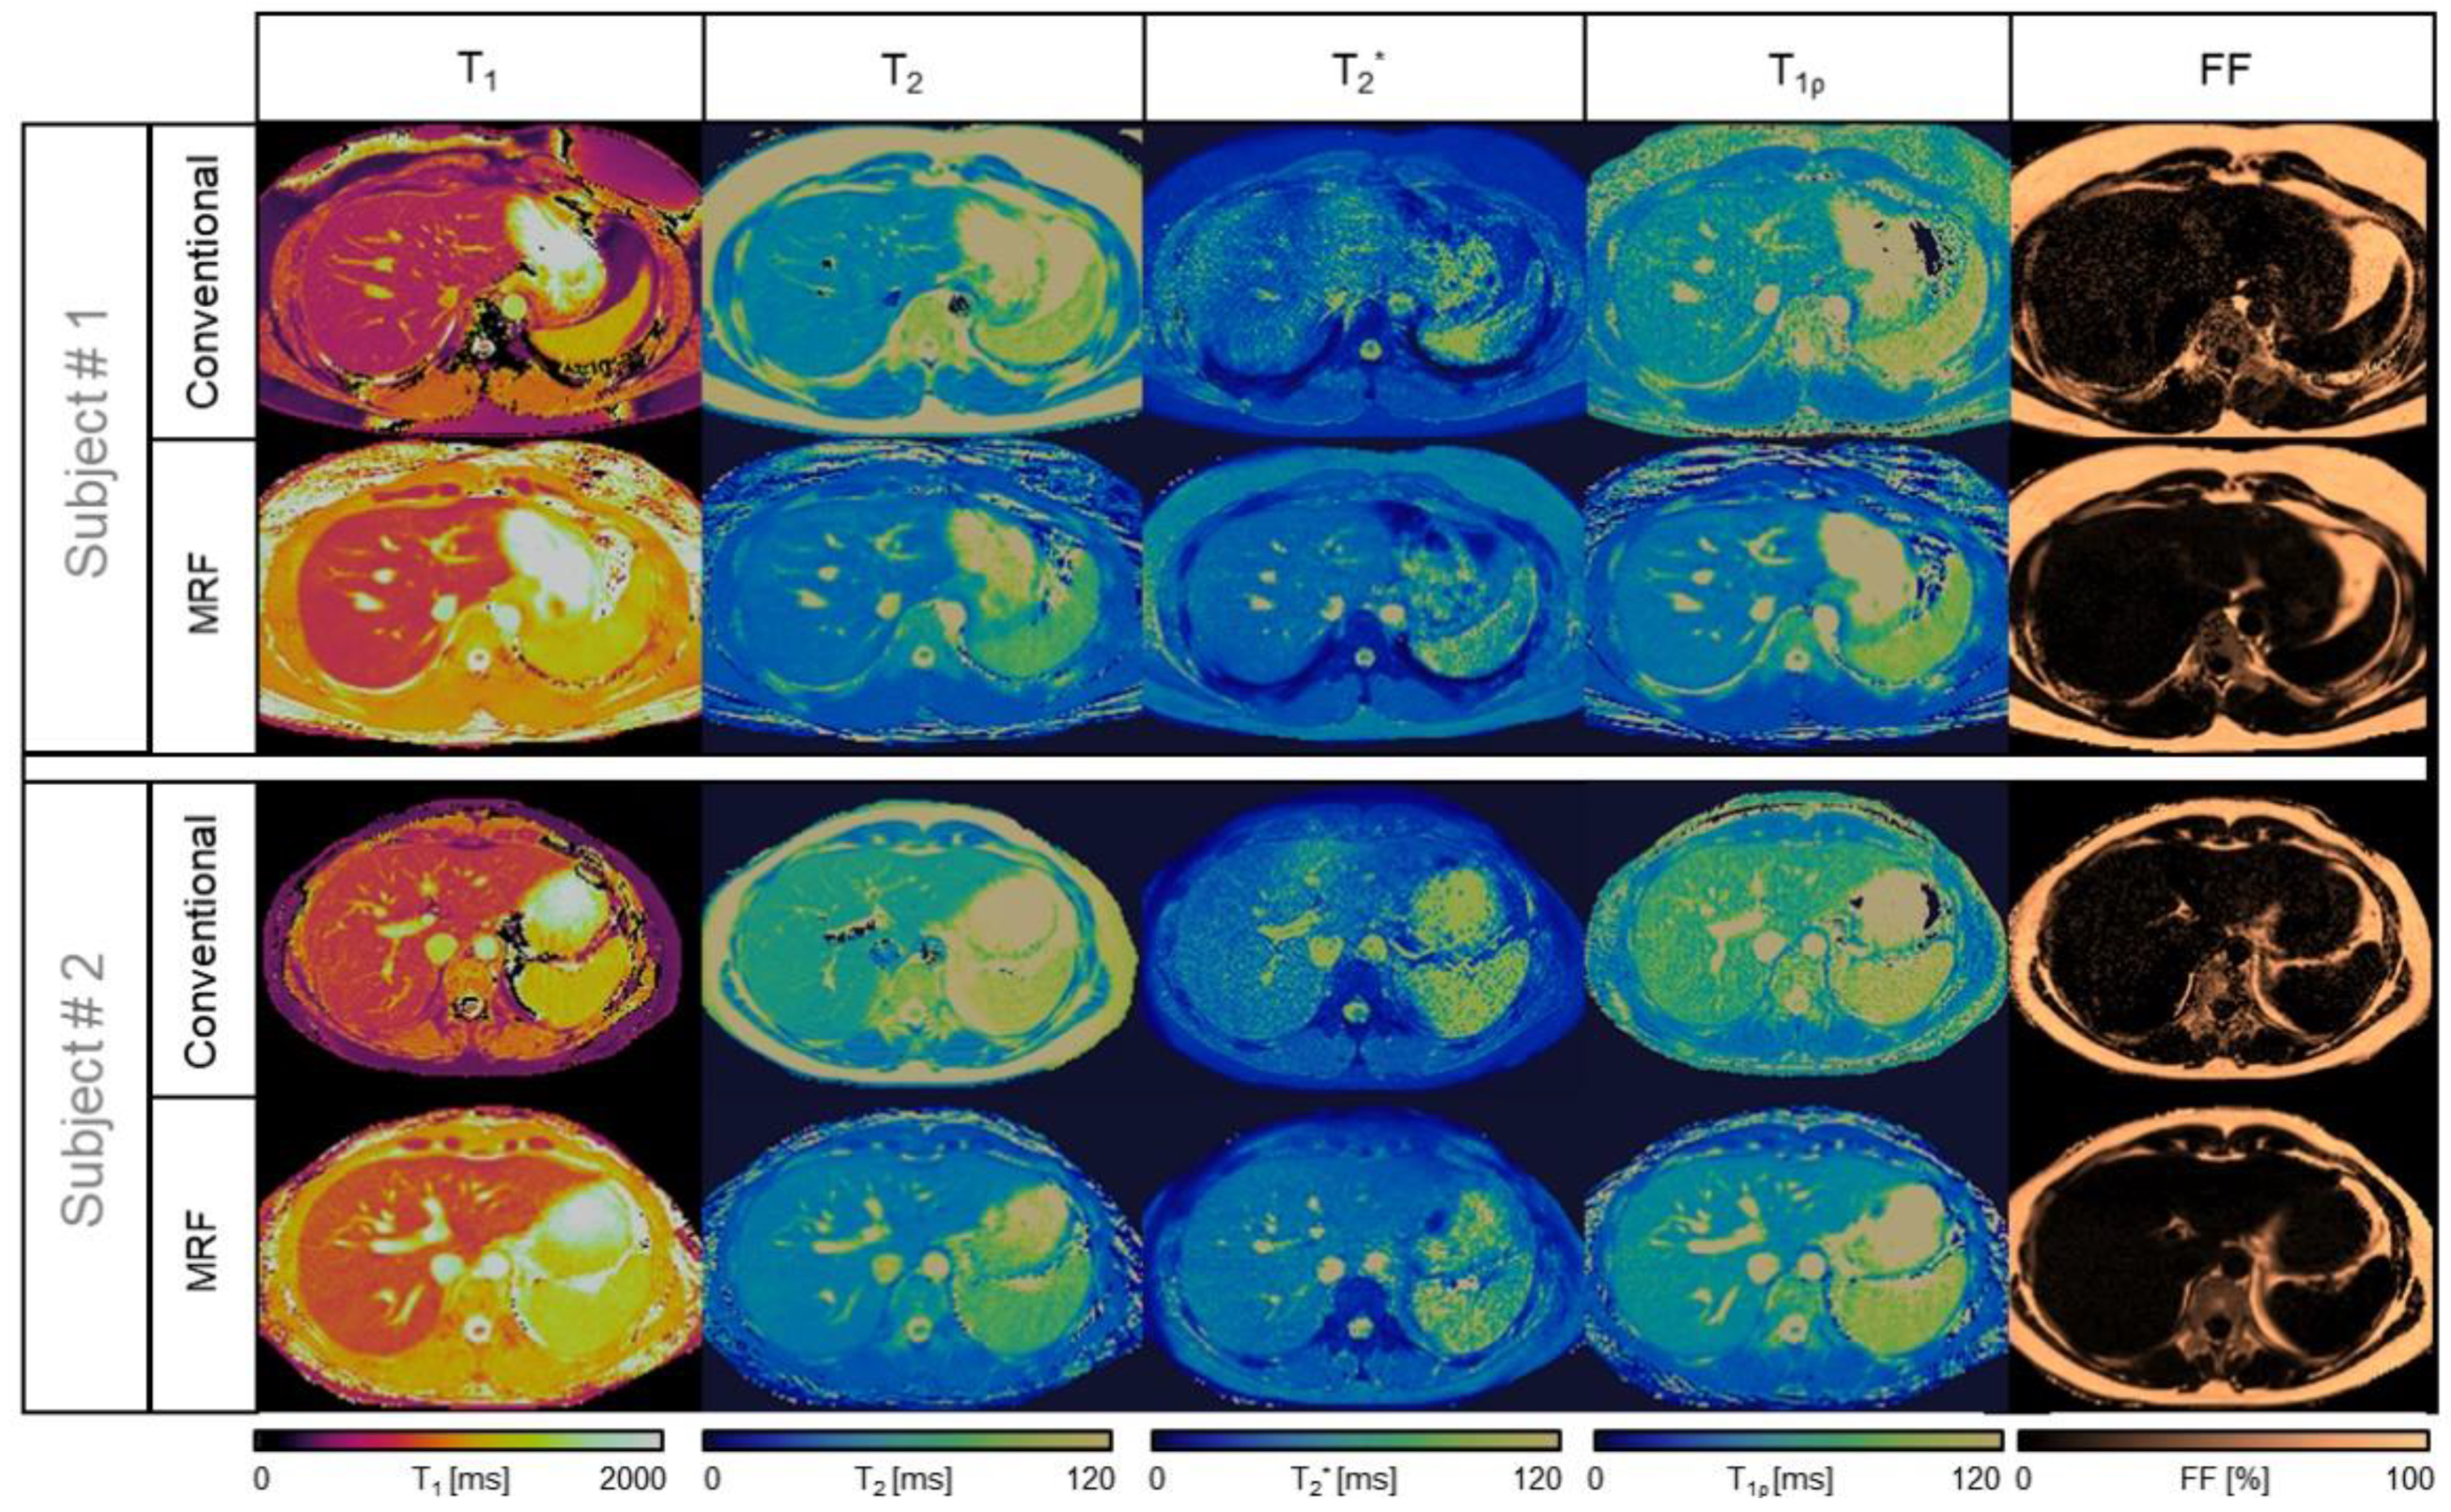

- Chen, Y.; Jiang, Y.; Pahwa, S.; Ma, D.; Lu, L.; Twieg, M.D.; Wright, K.L.; Seiberlich, N.; Griswold, M.A.; Gulani, V. MR Fingerprinting for Rapid Quantitative Abdominal Imaging. Radiology 2016, 279, 278–286. [Google Scholar] [CrossRef] [PubMed]

- Jaubert, O.; Arrieta, C.; Cruz, G.; Bustin, A.; Schneider, T.; Georgiopoulos, G.; Masci, P.; Sing-Long, C.; Botnar, R.M.; Prieto, C. Multi-parametric liver tissue characterization using MR fingerprinting: Simultaneous T1, T2, T2*, and fat fraction mapping. Magn. Reson. Med. 2020, 84, 2625–2635. [Google Scholar] [CrossRef] [PubMed]